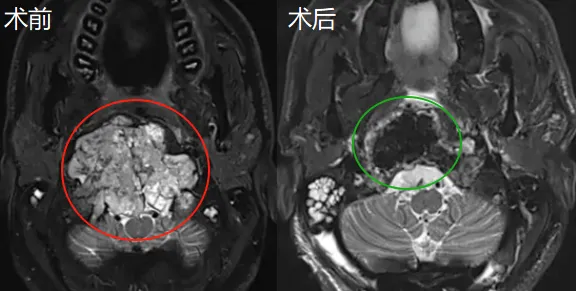

杰森的手术如期进行。福教授考虑到肿瘤已导致颅颈交界区骨质结构的广泛破坏和侵蚀,因此,他选择了远外侧经髁入路,通过显微镜和神经内镜的“双镜联合”技术切除肿瘤。

03显微镜+神经内镜:成功全切肿瘤

将神经内镜通过显微镜下创建的通道引入手术区域,利用其广角视野探查显微镜下难以直视的死角和深部结构,从而进一步确认肿瘤边界,精细切除显微镜下难以完全暴露的肿瘤对侧部分,最终实现巨大肿瘤的完全切除。

术后,杰森的吞咽功能得到了显著改善,颈部的疼痛也有所减轻。但是——“医生,为什么我的颈椎里多了几枚螺钉?”

术后的杰森在听闻肿瘤全切的好消息后再一次迷茫了。没想到,福教授笑着说:“由于肿瘤位于颅颈交界处,术前评估时我们认为手术后可能会出现颅颈不稳定,所以才在你的颈椎处打了螺钉,这是为你好呀!”